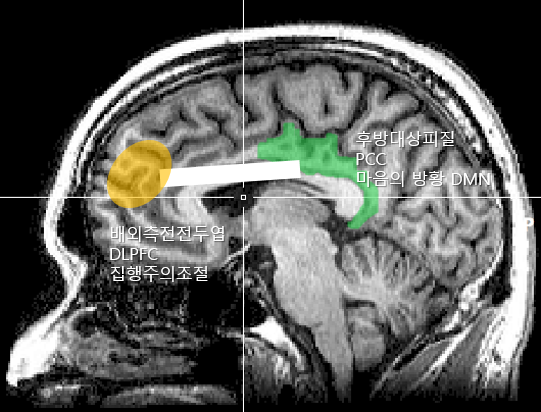

평소 명상이 가장 좋은 휴식법이라고 주장한다. 명상을 하면 주의를 조절하는 뇌 부위를 제외하고 전반적인 뇌 활동이 줄어든다. 뇌가 조용해진다. 그리고 쉴 때도 활성화되는 디폴트 모드 네트워크(DMN)의 활성도 억제된다. 명상을 하면 마음이 방황하게 하는 디폴트 모드 네트워크(DMN)의 핵심 노드인 후대상피질(PCC)과 주의를 제어하는 배외측전전두엽(DLPFC)의 기능적 연결이 강해지면서 주의력이 향상되고 마음의 방황이 줄어들게 된다(DMN억제). 보다 명료한 상태에서 완벽하게 뇌가 휴식할 수 있도록 해준다.

그림1.png